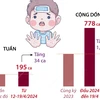

[Số người tử vong vì ngộ độc rượu có Methanol tăng vọt từ năm 2016]

Ngộ độc rượu gia tăng chóng mặt

Thạc sỹ Nguyễn Trung Nguyên – Phụ trách Khoa Chống độc (Bệnh Viện Bạch Mai) cho hay, trước đây số ca ngộ độc rượu có rất ít. Kể cả rượu nấu theo phương pháp thủ công cũng không gây ra nhiều ca ngộ độc hàng loạt như trong thời gian gần đây.

Từ sau Tết Nguyên đán đến nay, có 4 chùm ca bệnh ngộ độc rượu được cấp cứu tại Bệnh viện Bạch Mai.

Chùm ca 1 xảy ra vào tháng Một, địa điểm quanh bệnh viện 198: có ba bệnh nhân đều tử vong. Chùm ca 2 cũng xảy ra tại Hà Nội vào tháng Hai, có 4 bệnh nhân thì có 2 trường hợp tử vong. Chùm ca ngộ độc rượu thứ 3 xảy ra vao cuối tháng Hai đầu tháng Ba với 6 bệnh nhân thì có 1 trường hợp tử vong.

Chùm ca ngộ độc rượu thứ 4 xảy ra ở Cầu Giấy với 9 bệnh nhân là sinh viên.

Kết quả phim chụp não của một bệnh nhân ngộ độc rượu Methanol đang điều trị tại Bệnh viện Bạch Mai bị tổn thương nặng nề. (Ảnh: Thùy Giang/Vietnam+) Thống kê của Cục An toàn Thực phẩm (Bộ Y tế) cho thấy số ca ngộ độc rượu Methanol đang có xu hướng gia tăng nhanh do tình trạng lạm dụng rượu tràn lan. 10 năm qua, toàn quốc có 382 người bị ngộ độc do sử dụng rượu không an toàn, làm 98 người chết (thống kê này không bao gồm ca ngộ độc rượu lẻ tẻ).

Chỉ riêng 3 tháng đầu năm, cả nước ghi nhận 3 vụ ngộ độc do rượu methanol, với 78 người mắc và gần 20 người tử vong. Trong đó riêng ngộ độc rượu tập thể tại Lai Châu vào tháng 2 đã có đến 10 người thiệt mạng, 68 người mắc. Trong khi năm 2016 không ghi nhận vụ nào, năm 2015 có 2 vụ ngộ độc rượu methanol nhưng chỉ có 5 người mắc và 1 tử vong.

Bác sỹ Nguyên phân tích, đặc điểm chung của các bệnh nhân là tất cả lạm dụng hoặc nghiện rượu, hầu hết, 32/34 bệnh nhân - chiểm tỷ lệ 92% uống rượu không có nhãn mác, không có nguồn gốc xuất xứ rõ ràng. Tính chất ngộ độc tập thể đang ngày càng gia tăng, bao gồm công nhân và sinh viên. Các bệnh nhân có các biểu hiện muộn sau khi uống, nên đến bệnh viện muộn và trong tình trạng nặng.

Phần lớn các ca ngộ độc rượu sẽ tử vong hoặc di chứng nếu không được điều trị. Bệnh nhân nhập viện với các biểu hiện như: đau đầu, buồn nôn, mờ mắt, hôn mê. Có 19/34 ca trong tình trạng hôn mê khi đến viện, 100% ca bệnh nhiễm toan chuyển hoá nặng.